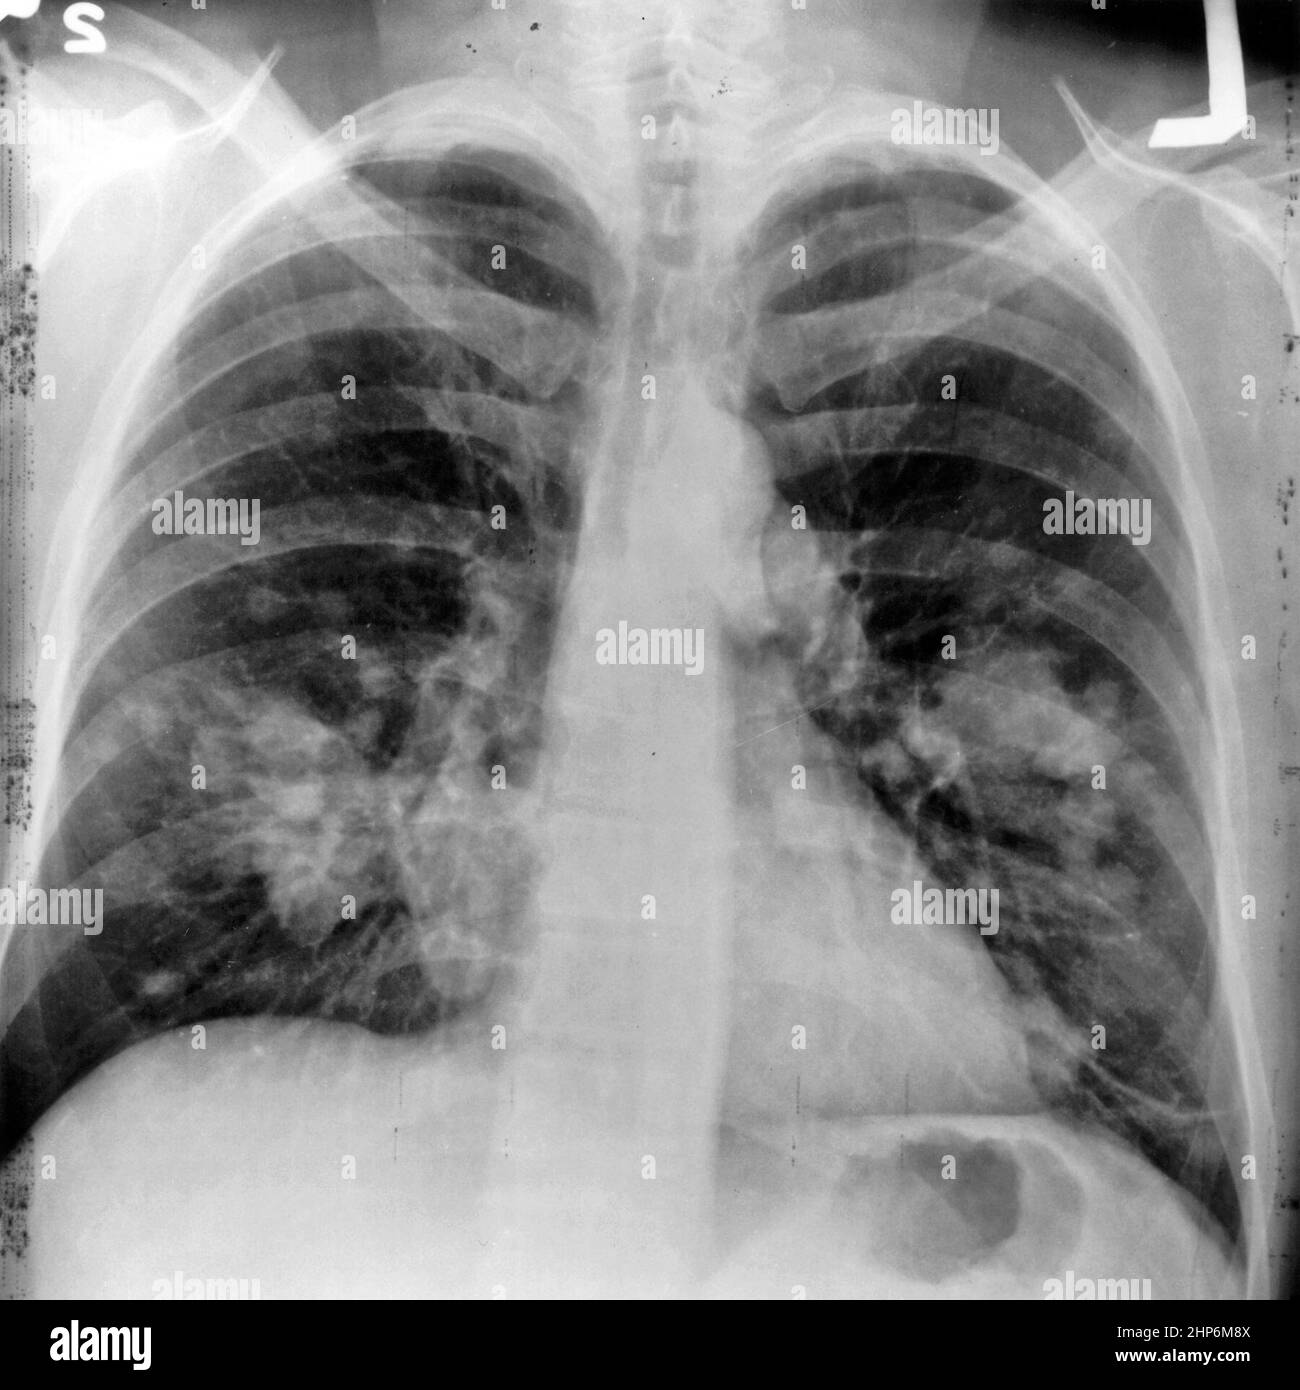

An xray image of a chest. Both sides of the lungs are visible with a Could Chest Pain Be Lung Cancer learn how lung cancer can cause pain in the chest and lower back, and how to manage it with medicines, therapies, and palliative. lung cancer is the most common cancer in the world, and pain is the most common symptom of lung cancer. learn about the common and less common symptoms of lung cancer, such as cough,. Could Chest Pain Be Lung Cancer.